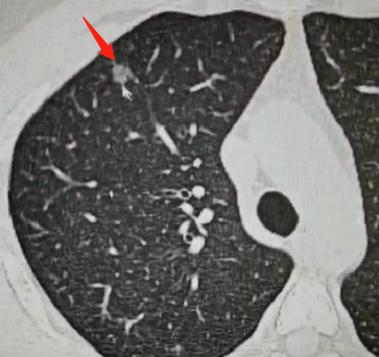

很多朋友拿到CT报告,看到“多发”两个字就很紧张,经常有人咨询我:“多发到底是有